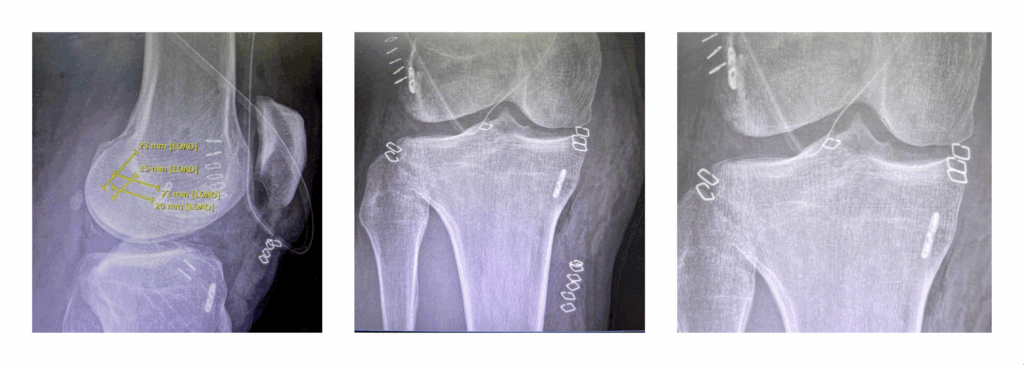

Nel presente articolo approfondiamo un caso specifico di una paziente di 15 anni, giocatrice di basket, operata con tecnica di ricostruzione All-Inside e plastica antero-laterale con tecnica GRAAL (Gracilis Anatomic Anterolateral Ligament Reconstruction).

A differenza delle tecniche tradizionali che prevedono l’effettuazione di tunnel ossei che attraversano tibia e femore, la tecnica All-Inside prevede degli Half-tunnel (tunnel incompleti che rispettano maggiormente l’osso corticale). Si tratta di una soluzione estremamente anatomica che preserva le cartilagini di accrescimento. Il trapianto (generalmente il tendine semitendinoso quadruplicato prelevato dallo stesso paziente, come in questo caso, oppure come t. quadricipitale e altri) viene fissato all’interno di questo half tunnel con sistemi in sospensione come bottoni o placchette, evitando di creare un tunnel tibiale completo di uscita.

Nel paziente in esame, soggetto sportivo con attività fisica rilevante, alla ricostruzione con Tecnica All-Inside è stata associata una plastica extra-articolare laterale con Tecnica GRAAL, volta a rinforzare l’articolazione del ginocchio evitando eventuali sensazioni di instabilità nella rotazione e preservando maggiormente il crociato da futuri eventi di rottura.

Si tratta di una delle più recenti tecniche di rinforzo del complesso legamentoso Antero-laterale, particolarmente nota per la sua efficacia. Si basa sull’utilizzo del tendine gracile, con il quale il chirurgo specialista crea un nuovo legamento, che viene posizionato anatomicamente per contrastare l’eccessiva rotazione interna della tibia.